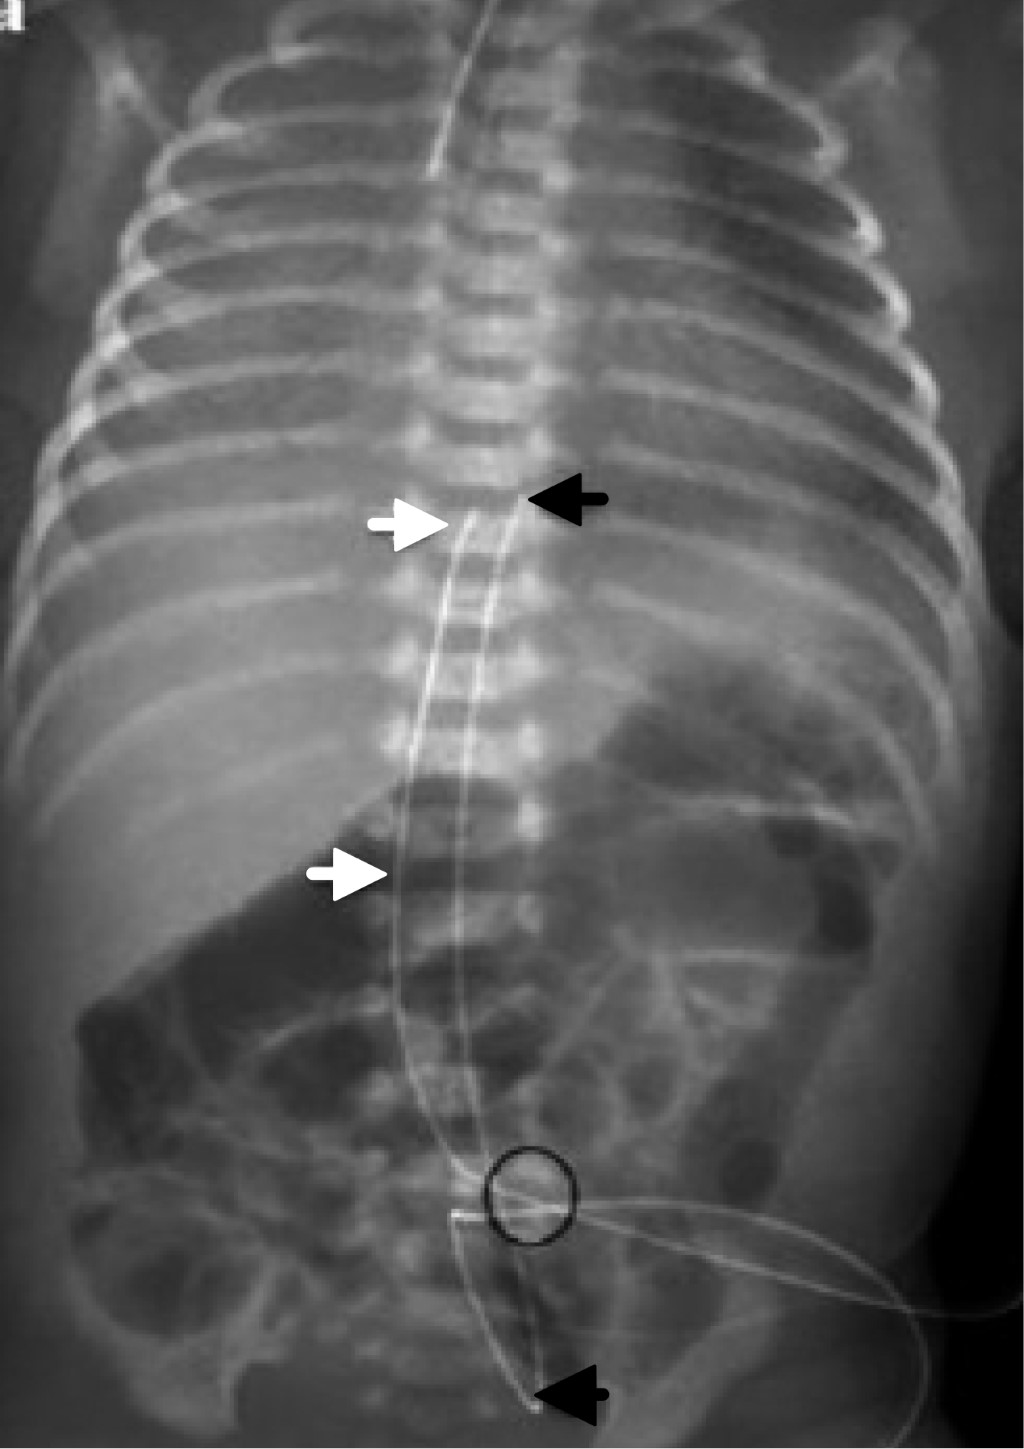

• 2. Se pueden diferenciar radiológicamente por su trayecto anatómico, el catéter venoso al entrar a pared abdominal se dirige hacia dirección cefálica y se sitúa en el lado derecho de abdomen y el arterial al entrar a pared abdominal se dirige hacia dirección podálica, de tal forma que baja para entrar a la arteria iliaca interna derecha o izquierda y hace un bucle para ascender por las iliacas y llegar a la arteria aorta, situándose ligeramente por el lado izquierdo del abdomen.

• 6. En una radiografía tangencial de abdomen y tórax, los catéteres tienen una distribución muy particular, el venoso se dirige siempre hacia dirección cefálica, hacia arriba por la pared abdominal anterior para pasar a un lado del hígado y llegar al corazón derecho. El catéter arterial se dirige siempre hacia dirección podálica, hacia abajo de la pared abdominal hasta alcanzar la arteria iliaca interna derecha o izquierda y de esta forma ascender para llegar a la arteria aorta, haciendo un bucle y correr por encima de los cuerpos vertebrales lumbares y dorsales (Figuras 12 y 13).

• 1. Posición anómala: provoca complicaciones relativamente menores y otras potencialmente mortales. En muchas ocasiones es necesario solicitar otras proyecciones radiológicas para tener una interpretación correcta. Ante la duda, pedir apoyo a personal con mayor experiencia o a un experto radiólogo. El catéter umbilical venoso puede quedar enrollado en cualquiera de las cámaras del corazón e incluso por arriba de él (vena cava superior, vena yugular interna, vena innominada, venas pulmonares derechas o izquierdas, arteria pulmonar), o por debajo del hemidiafragma derecho (en el sistema venoso umbilical o en vena cava inferior) (Figura 14).

Figura 12

Figura 13